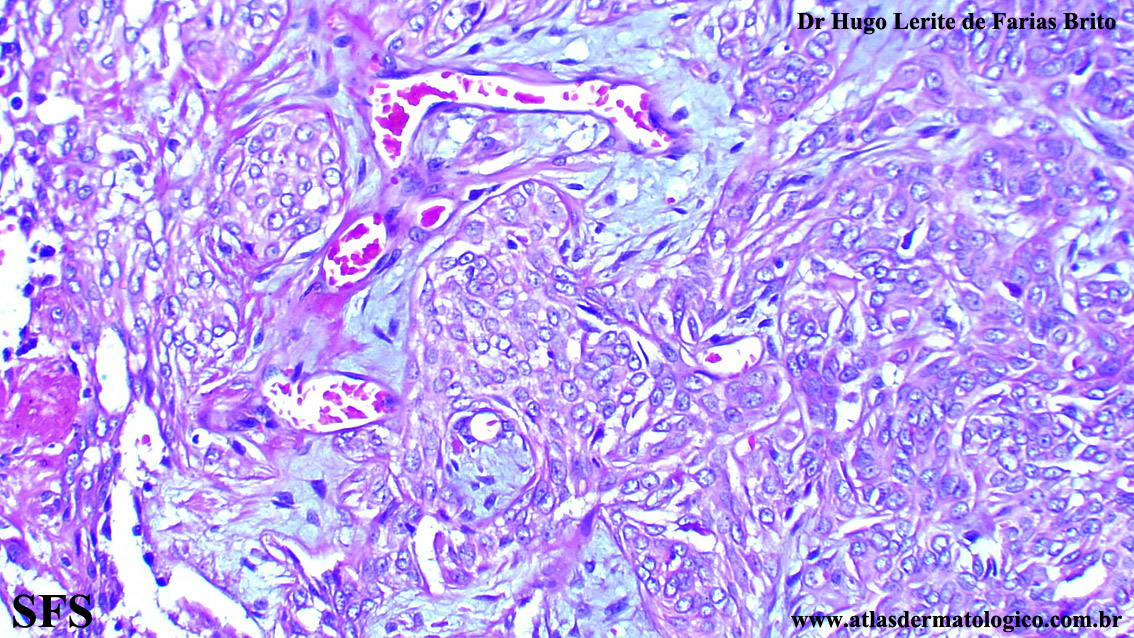

trichilemmoma-desmoplastic_trichilemmoma